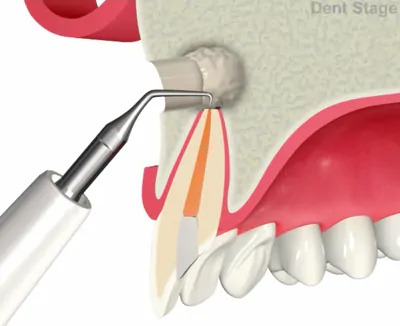

3抜髄

炎症を起こしてしまった神経を抜いていきます。この時使用するのはファイルというヤスリのようなものを使用します。

歯根端切除術

根管治療を行なっても症状が改善しない場合や根尖病巣が大きすぎて、根管治療では治せない場合等で行う施術方法です。歯茎を開いて、外科的な明視野で直接根尖病巣(歯根のう胞、歯根肉芽種)を取り除き、症状の改善を図ります。(※第一大臼歯までが適応です)

切開

骨の削除

炎症の除去

歯根の切断

薬剤充填

縫合